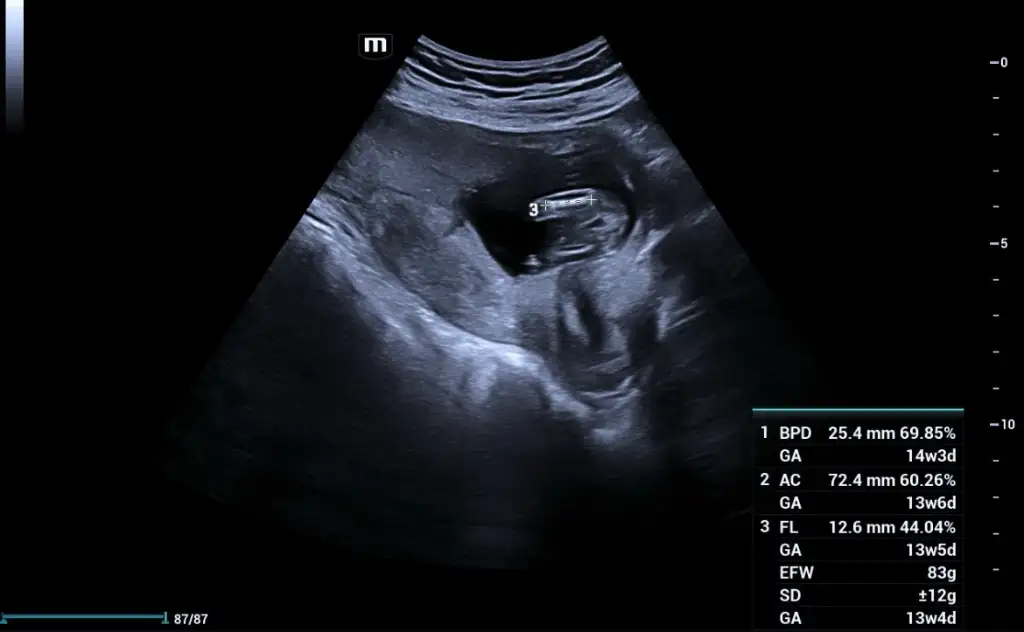

Merhaba yeni görüntüler var sizce ne olabilir doktorum bir tahminde bulundu ama sizin fikrinizi merak ediyorum

13+4 tahminde bulunabilir misiniz şimdiden teşekkür ederim.